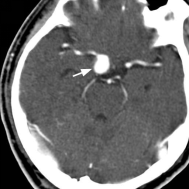

动脉瘤 颅内动脉瘤是指因为动脉局部薄弱、结构变化、外伤等因素导致颅内动脉管腔的局部异常扩张。多见于Willis环的动脉分叉部。是引起自发性蛛网膜下腔出血(SAH)最常见的原因。我国治疗的动脉瘤病人中95%都是破裂后出血才被发现和治疗。

未破裂的脑动脉瘤的CT典型表现 破裂的脑动脉瘤 CT表现(SAH)